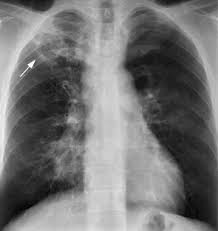

영국의 의사 리처드 모턴이 폐결핵이 '혹'(tubercles)과 관련이 있음을 규명했습니다.

이는 결핵이 폐에 작은 결절을 형성한다는 중요한 사실을 밝혀낸 것입니다.

독일의 미생물학자 로베르트 코흐가 '결핵균(Mycobacterium tuberculosis)'을 발견하는 데 성공했습니다.

이 업적으로 그는 1905년 노벨 생리학·의학상을 수상하며 인류 역사상 가장 치명적인 질병 중 하나의 원인을 밝혀냈습니다.